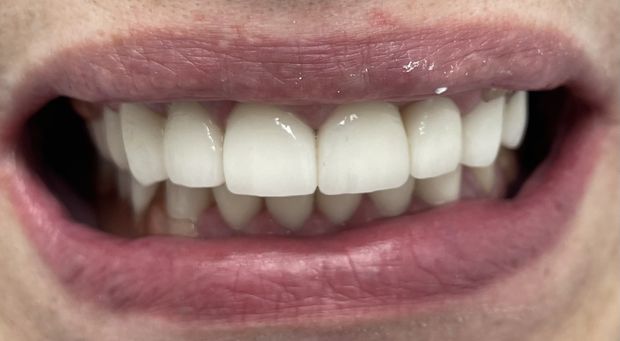

W tym przypadku zniszczonych i krótkich koron wykonano zabieg chirurgicznego wydłużenia koron klinicznych z plastyką dziąseł oraz wykonano pojedyncze korony cyrkonowe licowane porcelaną w kolorze BL2.